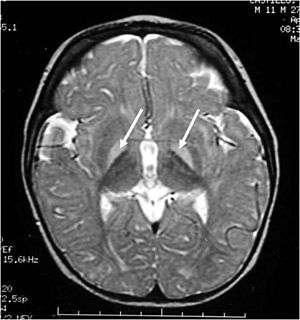

| MRI of the head. Hyperintense basal ganglia lesions on T2-weighted images. | |

These impairments are associated with lesions in the basal ganglia, auditory nuclei of the brain stem, and oculomotor nuclei of the brain stem.